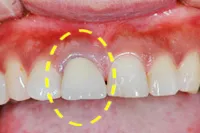

むし歯による前歯欠損の為来院されたケース

■治療前

■歯の根の引き上げ

■治療後

治療のポイント

歯の根の位置を引き上げ、抜歯。その日にインプラント治療へ。

自然の歯と変わらない審美性を取り戻し、非常に満足されています。

| 主訴 | 上顎の真ん中の歯が折れた |

| 治療方法 | 歯の根を引き上げることにより、増骨するので、その後1本のインプラントを埋入し治療した |

| 治療期間 | 約1年 |

| 通院回数等 | 10回 |

| 費用 | 550,000円(税込) |

| リスク・副作用 | 外科治療なしで増骨させた為、治療期間が長くなった |